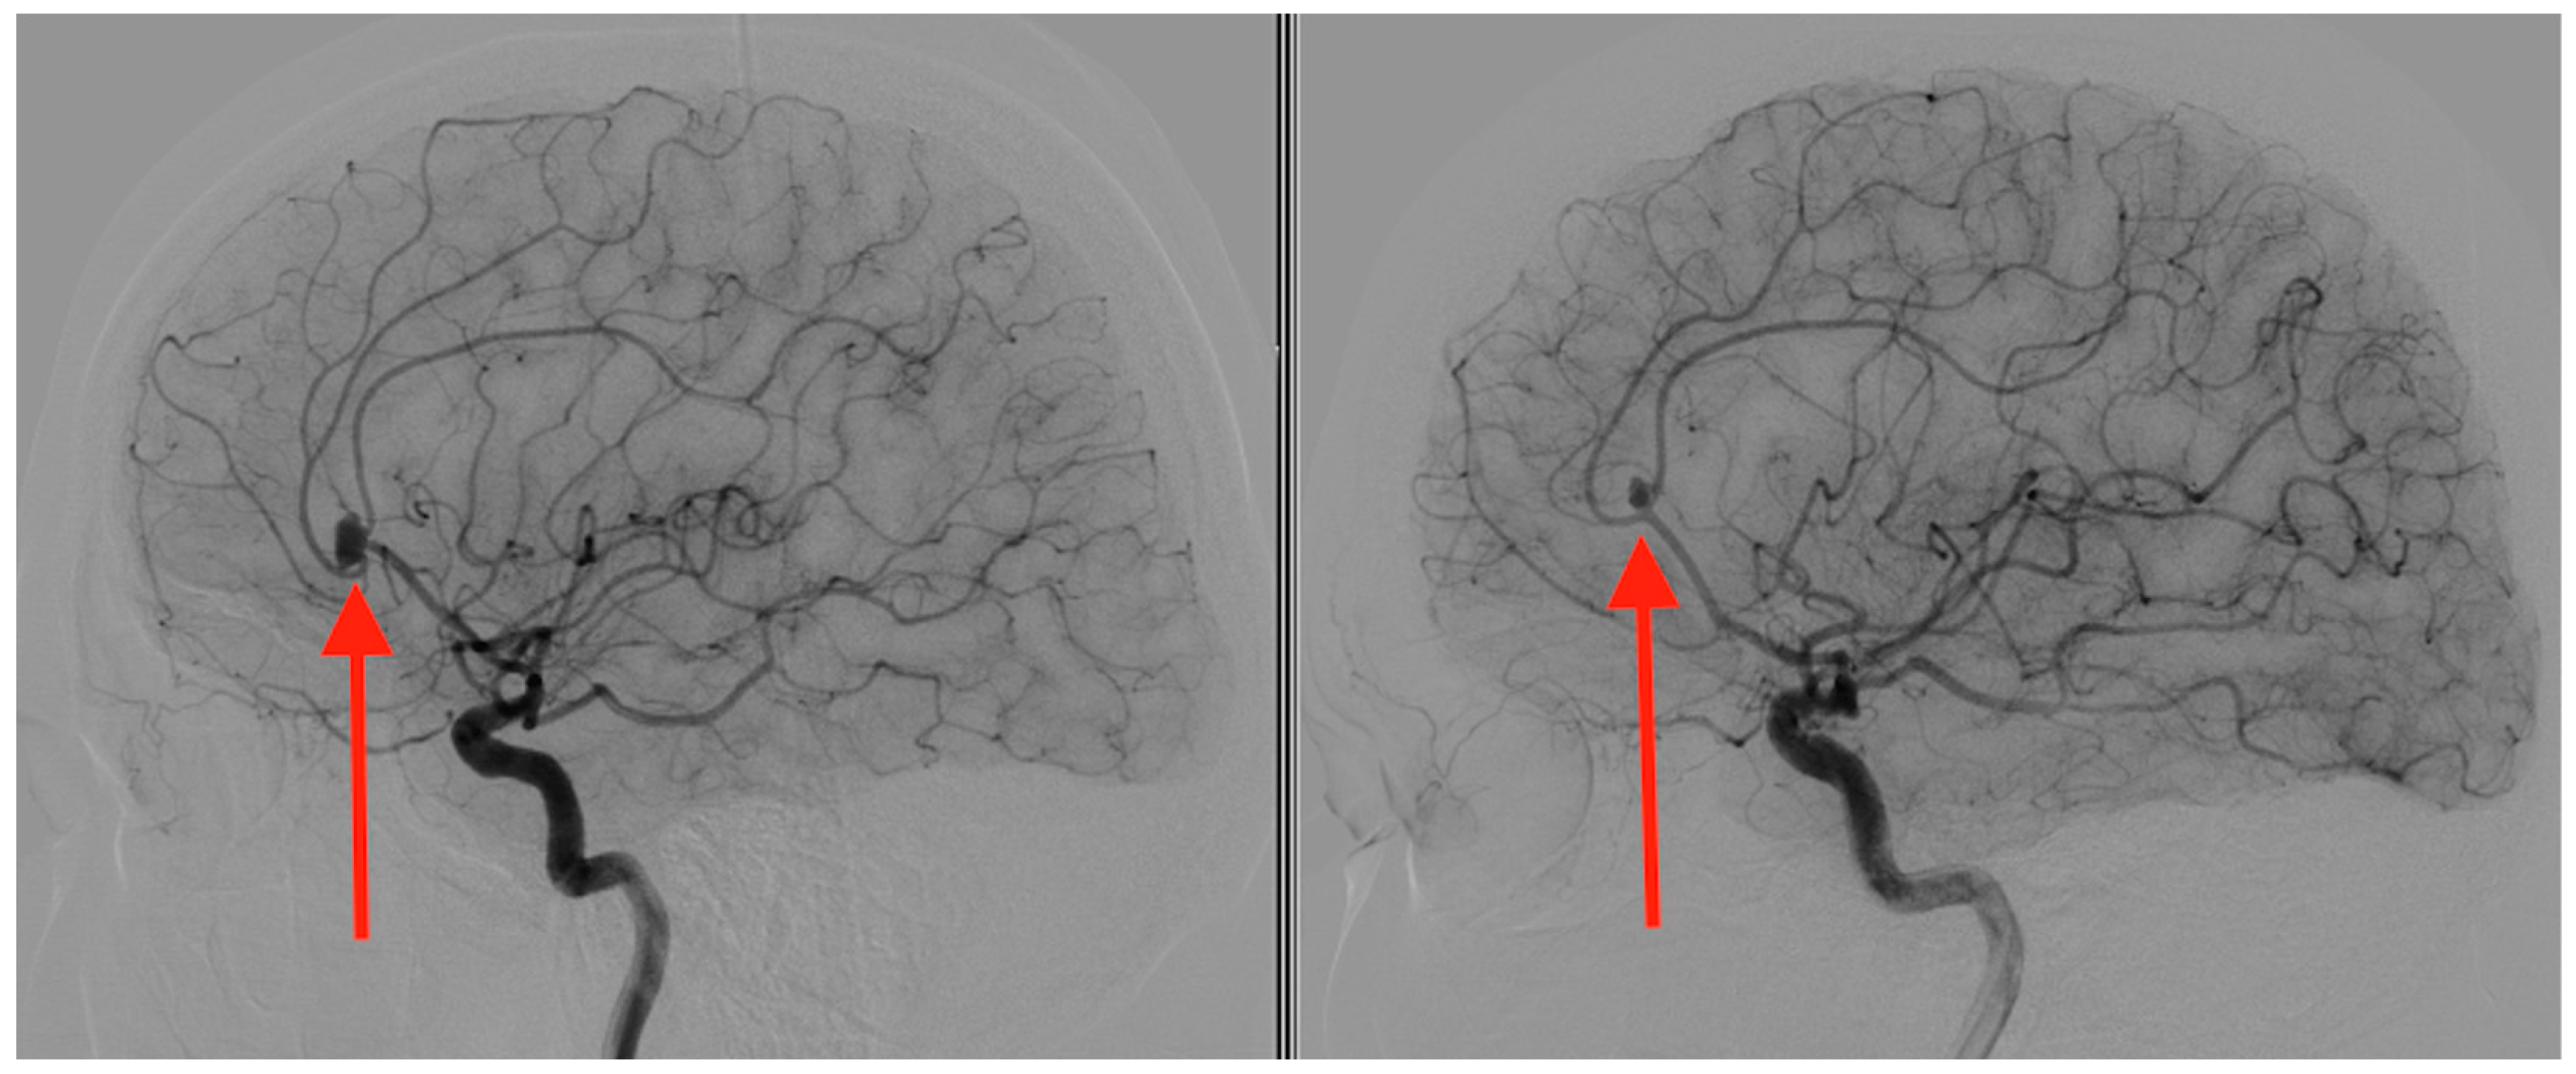

2. Case Presentation